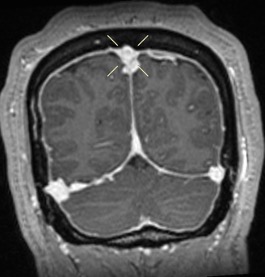

Diagnostic Testing. The patient’s CT brain imaging revealed a small amount of air in both frontal horns of the lateral ventricles (Figure 1). Her brain CTA revealed distension of the superior sagittal sinus (SSS), inferior sagittal sinus, transverse sinus, and vein of Galen and an extra-axial SSS defect (Figures 2-4). The initial report of the MRI brain with and without contrast redemonstrated trace pneumocephalus but was otherwise unremarkable. Later review after 10 days, revealed pachymeningeal enhancement, venous sinus distension, and a filling defect in the SSS suggestive of venous sinus thrombosis (Figures 5, 6). Her MRI of the cervical spine did not reveal another cause of neck pain, and her urine protein was negative.

Fig. 1. Nondependent pneumoventricle within the bilateral frontal horns of the lateral ventricles.